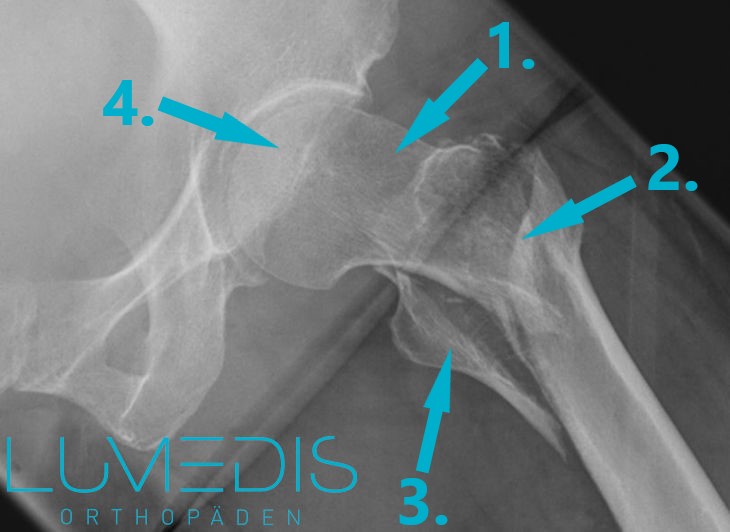

Röntgenaufnahme Hüfte a.p. links: